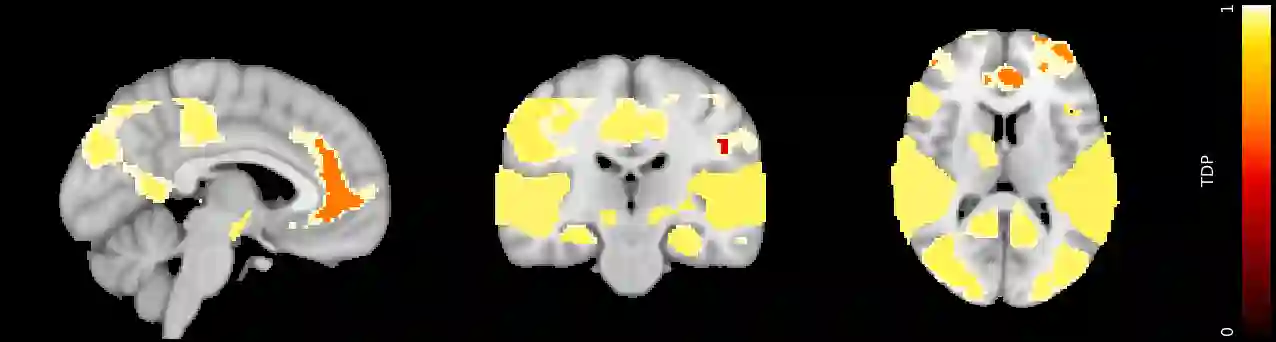

Sum-based global tests are highly popular in multiple hypothesis testing. In this paper we propose a general closed testing procedure for sum tests, which provides confidence lower bounds for the proportion of true discoveries (TDP), simultaneously over all subsets of hypotheses. Our method allows for an exploratory approach, as simultaneity ensures control of the TDP even when the subset of interest is selected post hoc. It adapts to the unknown joint distribution of the data through permutation testing. Any sum test may be employed, depending on the desired power properties. We present an iterative shortcut for the closed testing procedure, based on the branch and bound algorithm, which converges to the full closed testing results, often after few iterations. Even if it is stopped early, it controls the TDP. The feasibility of the method for high dimensional data is illustrated on brain imaging data. We compare the properties of different choices for the sum test through simulations.